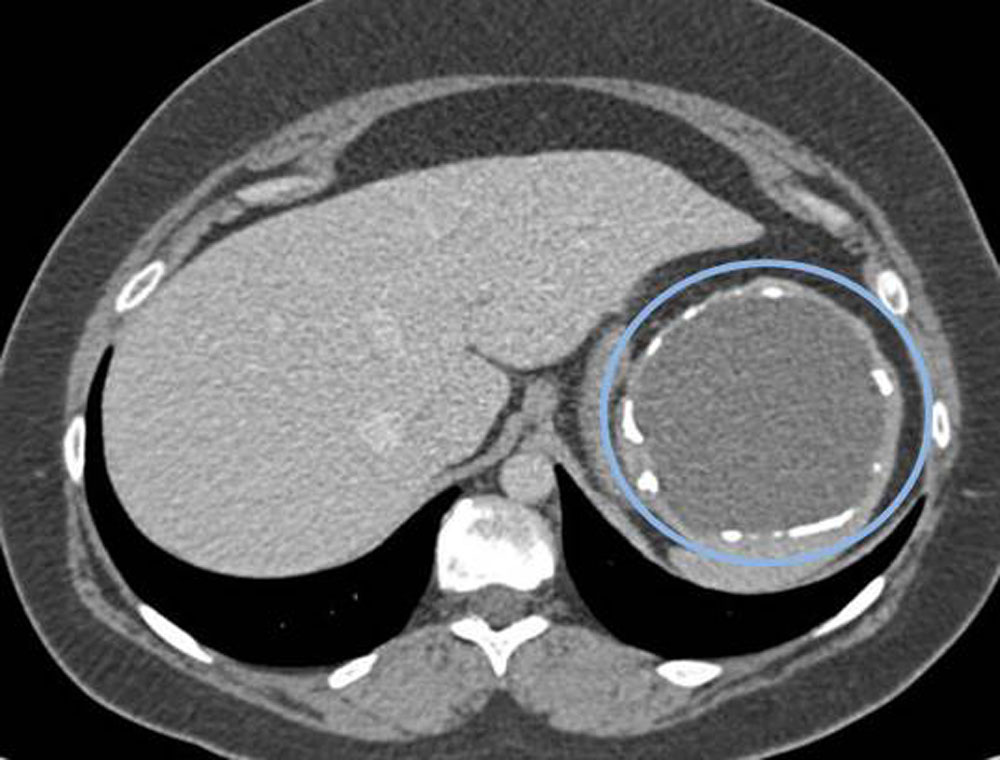

Причину возникновения кист достоверно установить получается не всегда. По происхождению кисты бывают паразитарные и непаразитарные. Паразитарные кисты являются следствием заражения организма паразитом, которым чаще всего является Эхиноккок (рис. 1).

С целью диагностики и определения тактики лечения используются лабораторные и инструментальные методы: стандартные анализы дополняются серологическими тестами на выявление паразитарной активности и опухолевыми маркёрами (СА19,9; РЭА); ультразвуковая диагностика, компьютерная томография с внутривенным контрастированием, магнитно-резонансная томография. В Пироговском Центре возможно прохождение всех этапов диагностики на самом современном оборудовании (рис. 3, рис. 4).